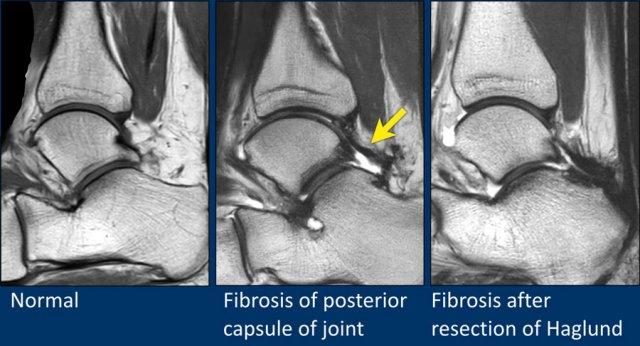

Khớp cổ chân được bao phủ bởi bao khớp.

Khi bao khớp bị dày lên, có thể gây ra hội chứng chèn ép (impingement) hoặc viêm màng hoạt dịch, như được thể hiện trên hình ảnh ở giữa.

Dày bao khớp có thể là hậu quả của chấn thương hoặc phẫu thuật trước đó.

Hình bên phải là một bệnh nhân xuất hiện xơ hóa sau phẫu thuật cắt bỏ gai xương Haglund.

Ghi nhận xơ hóa dọc theo mặt sau xương gót và bao khớp phía sau.

Ở bệnh nhân này chỉ ghi nhận tràn dịch lượng ít trong khớp cổ chân.

Trên các chuỗi xung không ức mỡ (non fatsat), có thể thấy hình ảnh dày nhẹ của bao khớp kèm theo các thay đổi phản ứng trong mô mềm xung quanh.

Bệnh nhân này có biểu hiện đau cổ chân phía trước do hội chứng chèn ép bởi bao khớp dày.

Đây là một ví dụ khác về dày bao khớp.

Trên các chuỗi xung ức mỡ (fatsat), có thể chỉ thấy hình ảnh phù nề trong lớp mỡ dưới da.

Tuy nhiên, trên các chuỗi xung không ức mỡ (non fatsat), có thể thấy rõ ràng mô xơ dày ở phía trước.

Dày bao khớp và các bất thường mô mềm thường được nhận diện rõ hơn trên các chuỗi xung không ức mỡ.

Trong trường hợp này, ghi nhận dày xơ hóa bao khớp (mũi tên).

Bệnh nhân có các thay đổi thoái hóa thứ phát trong khớp với phù nề xương dưới sụn và hình thành nang xương dưới sụn.

Đây là hậu quả của tình trạng va chạm lặp đi lặp lại của mô xơ vào xương trong quá trình gấp mu bàn chân.